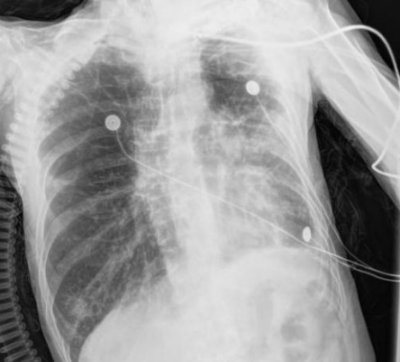

呼吸与危重症医学科救治。该科副主任朱锦琪、梁伟军及团队高度警觉免疫治疗病史可能带来的并发症,详细追溯他两年的免疫治疗用药记录,对其近期肺部CT影像进行反复对比和深入研判,认为其符合免疫检查点抑制剂相关肺炎(CIP)的典型表现,确诊其为迟发性、重度(4级)免疫检查点抑制剂相关肺炎。

免疫检查点抑制剂相关肺炎4级

明确诊断后,患者的治疗迎来关键转折点,团队迅速调整方案,启动大剂量糖皮质激素抗炎治疗,治疗效果立竿见影。患者的病情显著改善,氧合指数稳步上升,呼吸困难症状明显缓解。经过精心治疗,他在进入呼吸重症监护室一周后便转入呼吸科普通病房;10天后复查胸部CT,显示肺部弥漫性病变明显吸收好转,顺利出院。后续的定期随访复查也证实其肺部状况持续向好。

双肺病变持续吸收